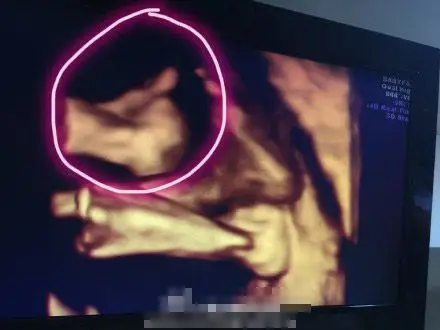

b超检查怀孕50天同卵双胞胎是这样的,孕妈看看你的双胞胎儿吧

彩超显示美双胞胎在妈妈肚子里甜蜜亲吻